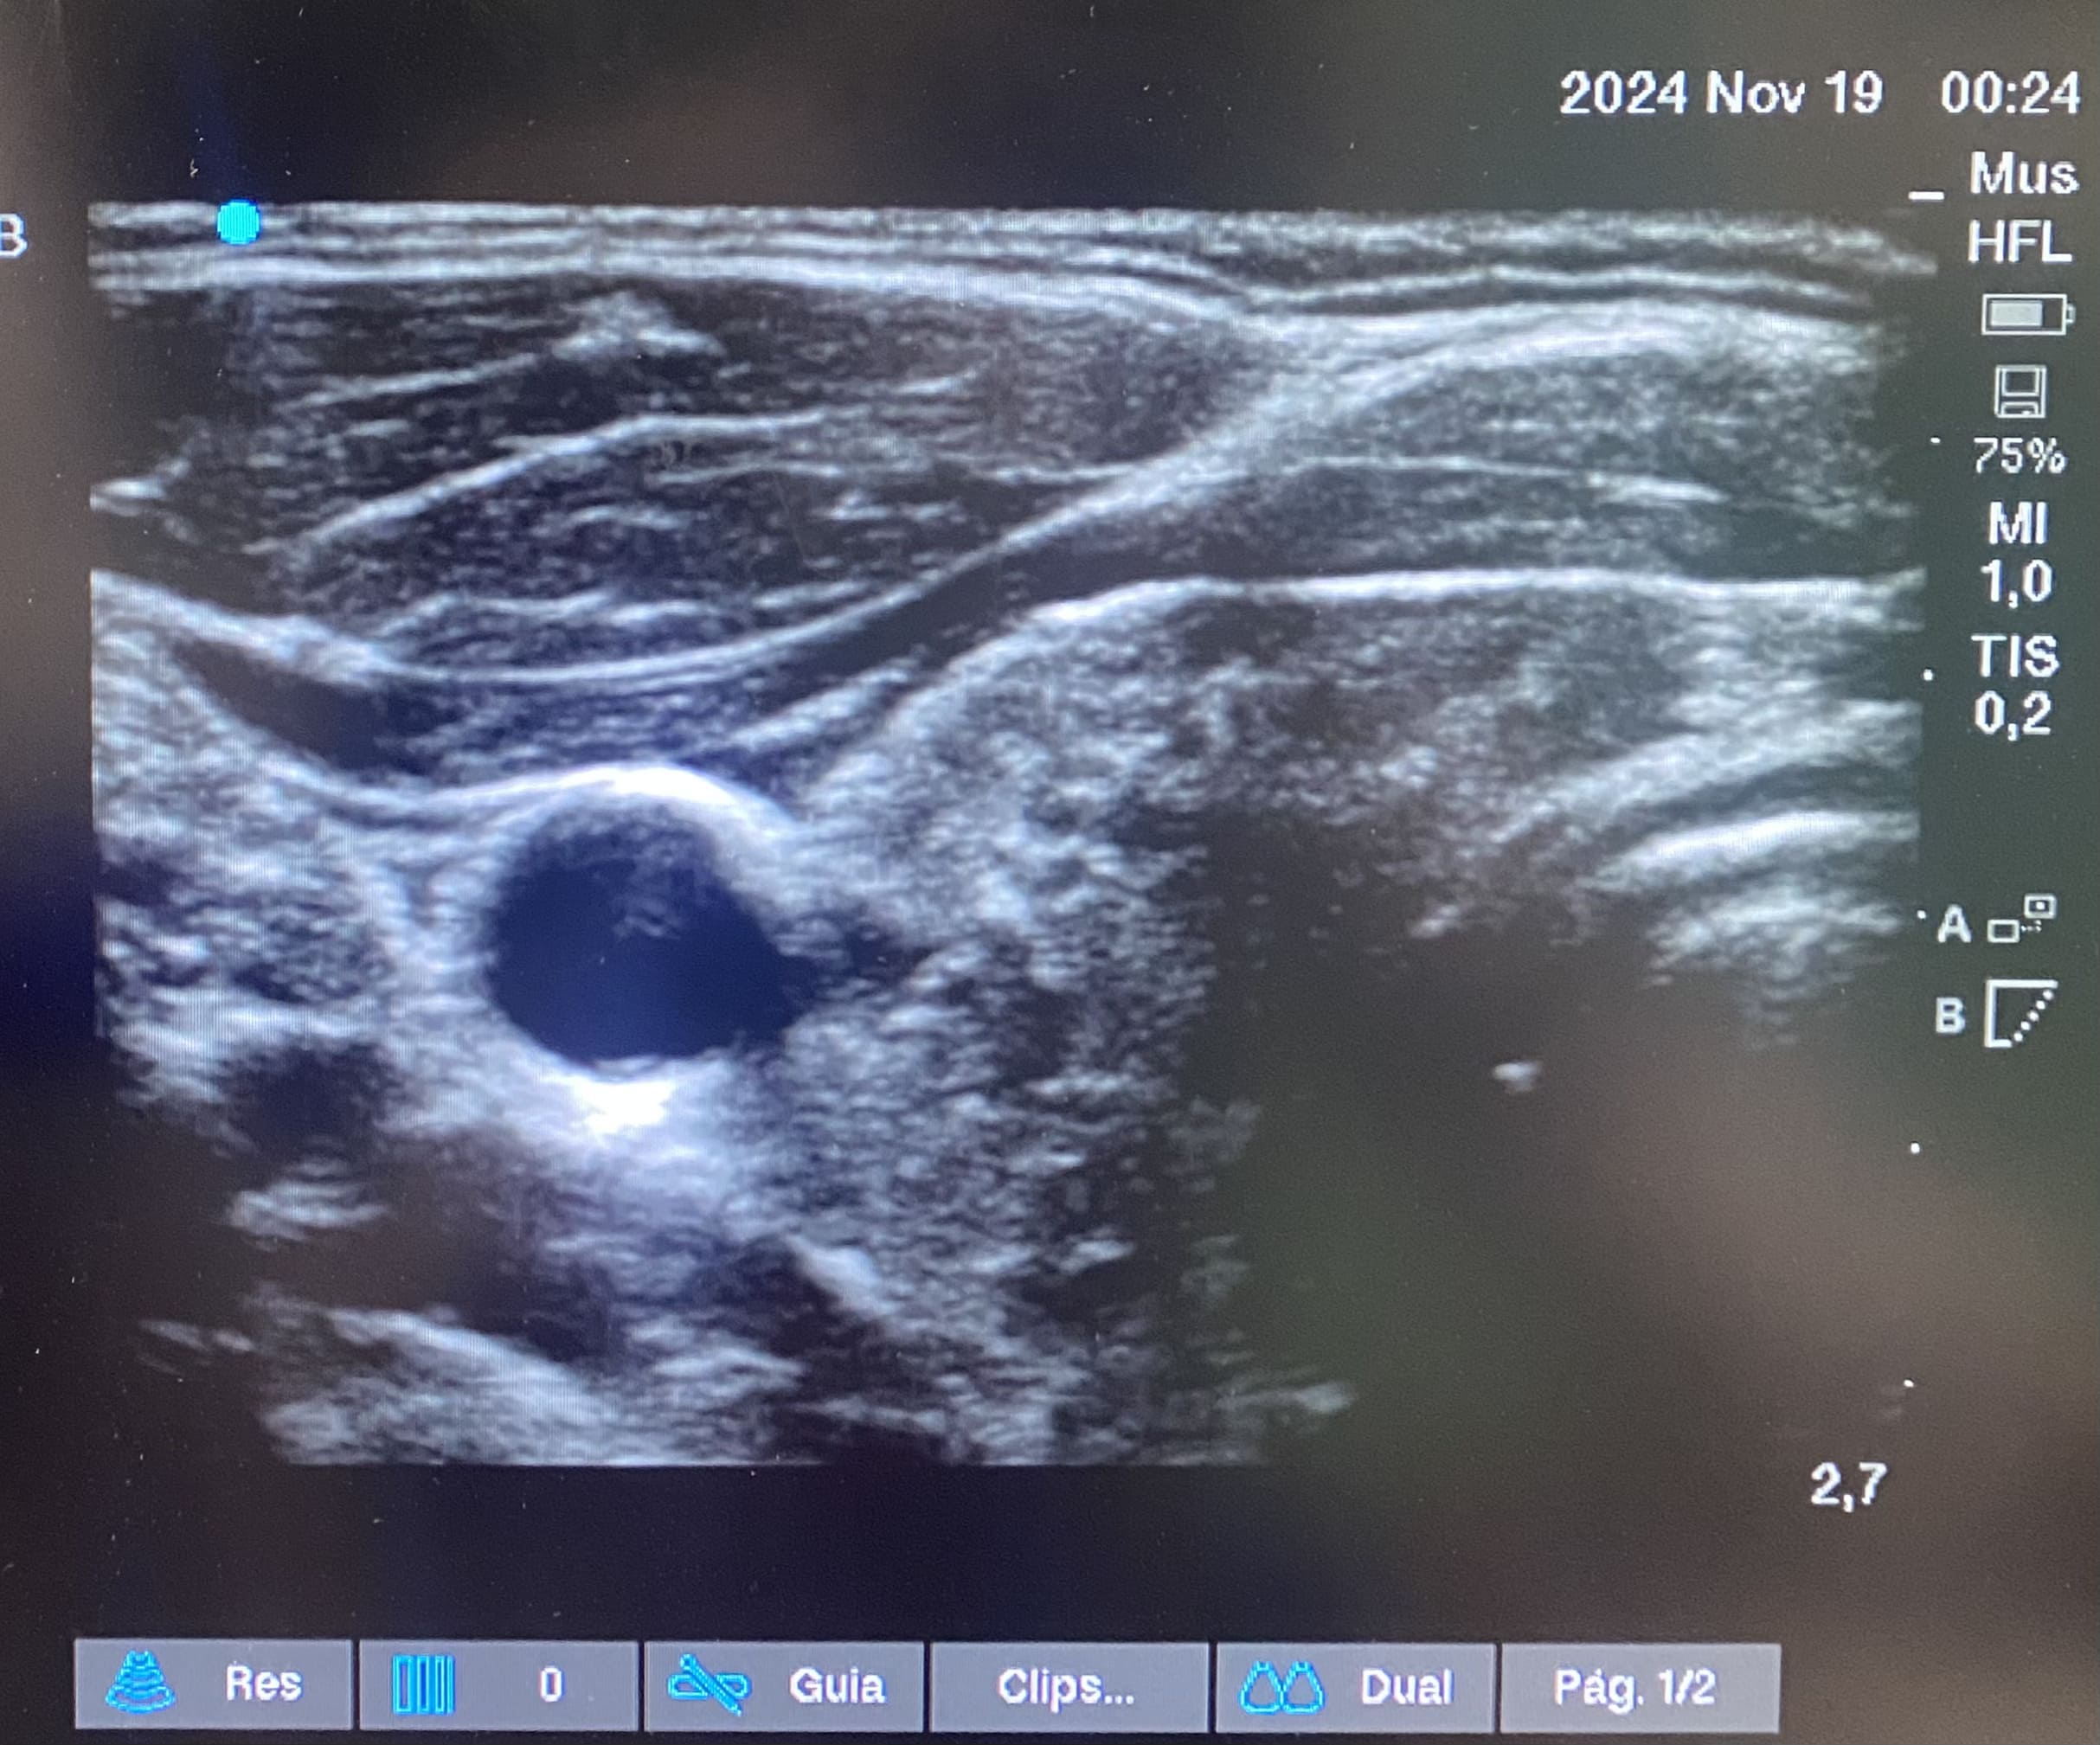

Planes de actuación: Se realiza ecografía en urgencias observándose glándulas tiroideas de tamaño normal con un patrón estructural alterado. Se inicia levotiroxina 50 mcg, se solicita ecografía reglada y anticuerpos (Ac) antitiroideos para control y seguimiento por su médico de atención primaria.

Ecografía de cuello-tiroides: Ambos lóbulos tiroideos presentan un tamaño dentro de la normalidad, con contorno lobulado, ecoestructura muy heterogénea con áreas seudonodulares y septos fibrosos y alguna pequeña formación quística. Hallazgos compatibles con tiroiditis probablemente autoinmune (valoración clínica y analítica).